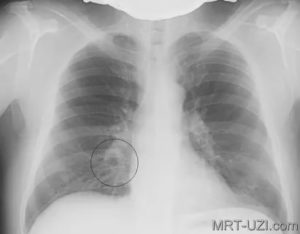

Очаговая пневмония характеризуется тенями неоднородной структуры, которые хорошо видны на снимке. Одинокие или множественные участки обычно размером до 1,5 сантиметра, неоднородные без четких границ.

Рентген-контроль при пневмонии данной формы врачи рекомендуют проходить спустя две недели после полного выздоровления. Осуществляется такая процедура для просмотра корней легких, которые расширяются при болезни и наполняются жидкостью.

Признаками очаговой пневмонии являются:

- нечеткие контуры тени;

- наличие жидкости в пораженной зоне;

- неоднородность участка инфильтрации.

Очаговая пневмония на рентгене характеризуется наличием жидкости в реберном синусе на стороне поражения. Среди всех форм пневмоний, очаговая является самой распространенной и зачастую она следует как осложнение после перенесенных респираторных заболеваний.